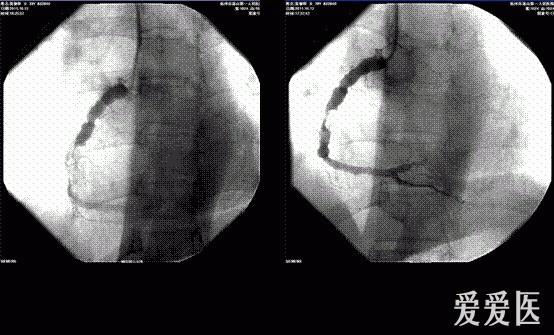

诊疗过程:2011.10.12急诊选择性冠脉造影,结果显示:左冠前降支轻度狭窄,右冠近端、中远段瘤样扩张,内径达10mm左右,右冠中段病变,95%狭窄,狭窄后血栓影,远端血流TIMI2级。将JR46F大腔导管送到右冠开口,送入0.014"runthrough导丝,跨过狭窄处送至右冠远端,然后沿引导钢丝送入抽吸导管到病变处多次抽吸,抽吸血液中可见少量血栓,血栓负荷明显减少,随后送入cordis2.5x15mm球囊,定位于狭窄段,8Kpa扩张球囊1次,重复造影显示残存狭窄85%,但后降支闭塞,0.014"runthrough导丝送入后降支,cordis2.5x15mm球囊8Kpa扩张后血流恢复,改用cordis3.5x15mm球囊定位右冠中段病变处,10kpa扩张后,残存狭窄仍有75%,右冠远端血流TIMI1级,试图进入另一根0.014"runthrough导丝,但在右冠近端瘤样扩张处受阻,结束手术,术中共用肝素针30mg,优维显130ml,期间病人无明显不适,撤出导管,拔除桡动脉鞘管加压包扎,送回病房,嘱右上肢制动,常规抗生素预防感染、心电图、心电监护、注意生命体征及伤口出血血肿和胸痛胸闷等情况。8药物治疗及检查:考虑患者右冠急性血栓形成,予替罗非班应用,同时监测凝血谱、血小板,根据凝血谱、血小板情况调整替罗非班剂量。术后患者血压偏低,一直予多巴胺针微泵维持血压。停用替罗非班针后继续予速碧林针4100iu q12h抗凝,拜阿司匹林片100mg qd、玻立维片75mg qd抗血小板,立普妥片20mg qd调脂,瑞安吉针改善心肌能量代谢,美卓乐片6mg qd治疗系统性红斑狼疮,泮托拉唑针抑酸护胃,阿魏酸哌嗪片、金水宝胶囊改善肾功能,补达秀片补钾。入院来患者一直血压偏低,多巴胺针小剂量维持下血压波动于90/60mmHg,心率70次/分,律齐,心电监护示:窦性心律,未见明显心律失常。2011.10.25停用多巴胺针后血压基本波动予90-100/55-65mmHg左右,患者又有心悸等自觉症状,心电监护可见窦性心律,频发室性早搏,复查心电图示窦性心律下壁、前侧壁、正后壁异常Q波伴ST-T改变。频发室性早搏,部分二联律电轴左偏提示左前分支传导阻滞 左胸导联低电压;急查血电解质K 3.1mmol/l,予静脉+口服加强补钾治疗,第二天复查血钾为4.0mmol/L,但室性早搏仍频发,继续予口服补钾及小剂量倍他乐克12.5mgbid口服后,患者心悸症状缓解不明显。2011.10.16动态心电图:窦性心律伴间歇性窦性心律不齐 房性早搏占<1%,为单发室性早搏占<1%,为单发ST-T改变。2011.10.20查心脏彩色多普勒+左心功能测定+室壁运动分析:(1)左室下壁局部收缩活动稍减弱;(2)主动脉瓣轻度返流;(3)二尖瓣轻度返流;(4)三尖瓣轻度返流;(5)肺动脉瓣轻度返流。(1)主动脉根部内径31舒张期室间隔厚度8左房内径29舒张期左室后壁厚度9左室舒张末期内径52射血分数(EF%)72.9左室收缩末期内径30。(2)左房左室内径正常,左室壁不增厚,静息状态下左室下壁局部收缩活动稍减弱。(3)二尖瓣不增厚,开放不受限,CDFI见轻度返流。二尖瓣血流图示E峰>A峰。(4)主动脉不宽,主动脉瓣不增厚,开放不受限,CDFI:见轻度返流,主动脉瓣瓣口最高流速约1.24m/s。(5)右心正常大,肺动脉内径20mm,CDFI:肺动脉瓣轻度返流,三尖瓣见轻度返流。CW据三尖瓣返流估测肺动脉收缩压23mmHg。2011.10.20心电图:窦性心律 下壁、前侧壁、正后壁异常Q波伴ST-T改变,请结合临床 左胸导联低电压。2011.10.30动态心电图:窦性心律 偶见房性早搏占<1% 室性早搏占15%部分呈三联律 前侧壁异常Q波伴ST-T改变,请结合临床与常规心电图.。

本帖最后由 新郑李永刚 于 2012-1-29 14:57 编辑 系统性红斑狼疮突发急性心肌梗塞救治一例 作者:吴瑰丽彭俊黄建振钱正明 一般情况:患者,女性,39岁 主诉:胸闷8小时入院。 现病史:患者8小时前突发胸闷不适,以胸骨下端憋闷为主,自觉憋闷区域约手掌大小,伴胸骨后压榨感,出冷汗,有恶心及呕吐1次,呕出少许胃内容物,无明显胸痛,无头晕、晕厥,无气急,无头痛等,症状呈持续性,经休息后稍有缓解。约100分钟后患者至我院急诊,急诊心电图提示:窦性心律、急性下壁、正后壁、高侧壁心肌梗死。心肌酶谱、肌钙蛋白:AST 21U/L LDH 270U/L CK 36U/L CK-MB 10U/L cTnI<0.01μg/L”,急诊考虑患者“急性心肌梗塞”,临时予阿司匹林片300mg嚼服、玻立维片300mg顿服等对症处理,并请心内科会诊及取得家属意见予尿激酶150万u溶栓治疗,溶栓2小时后复查心电图提示:窦性心动过缓,急性下壁正后壁心肌梗死。患者仍有胸闷不适,出汗多,心电图ST段下降不明显,考虑溶栓效果欠佳,经与家属沟通,取得知情同意后拟行“冠脉造影”检查及进一步治疗,拟“急性心肌梗死,系统性红斑狼疮”收住入院。病来意识清,精神软,未进食,小便自解,大便未解,体重未见明显增减。 既往史:既往体质偏弱,有“系统性红斑狼疮”病史32年,平时坚持服用美卓乐片。有“高血压病”病史4年,平时坚持服用安博维片,血压控制可。否认有“中风”病史,否认有“冠心病”病史,否认有“结核、肝炎”病史,否认有“肾炎,肾功能不全”等慢性肾脏病史,否认有“甲亢、糖尿病”病史,否认有药物、食物过敏史,否认外伤手术史,否认有输血史,常规预防接种。 家族史:父母均健在,母患“帕金森病”,父患“高血压病”,有一哥哥,体健,否认家族内遗传性、传染性疾病史。 体格检查:T37.5℃,BP 107/63mmHg,SPO2 100%,意识清,精神软,平卧位休息,颈静脉充盈,双肺呼吸音低,未闻及干湿啰音,心音低,心律欠齐,可及早搏,心脏各瓣膜听诊区未闻及明显杂音;腹软,无压痛反跳痛,肝脾肋下未及;双下肢不肿,双巴氏征未引出。 辅助检查:心电图(2011.10.12 14:03)示:窦性心律、急性下壁、正后壁、高侧壁心肌梗死。心肌酶谱肌钙蛋白(2011.10.12 14:17)AST21U/L LDH270U/L CK36U/L CK-MB10U/L cTnI<0.01μg/L。 入院诊断:1、急性下壁心肌梗死,KillipsⅠ级;2、系统性红斑狼疮;3、高血压病2级(极高危组)。 诊疗经过:2011.10.12急诊选择性冠脉造影,结果显示:左冠前降支轻度狭窄,右冠近端、中远段瘤样扩张,内径达10mm左右,右冠中段病变,95%狭窄,狭窄后血栓影,远端血流TIMI2级。将JR46F大腔导管送到右冠开口,送入0.014"runthrough导丝,跨过狭窄处送至右冠远端,然后沿引导钢丝送入抽吸导管到病变处多次抽吸,抽吸血液中可见少量血栓,血栓负荷明显减少,随后送入cordis2.5x15mm球囊,定位于狭窄段,8Kpa扩张球囊1次,重复造影显示残存狭窄85%,但后降支闭塞,0.014"runthrough导丝送入后降支,cordis2.5x15mm球囊8Kpa扩张后血流恢复,改用cordis3.5x15mm球囊定位右冠中段病变处,10kpa扩张后,残存狭窄仍有75%,右冠远端血流TIMI1级,试图进入另一根0.014"runthrough导丝,但在右冠近端瘤样扩张处受阻,结束手术,术[根据相关法规进行屏蔽]用肝素针30mg,优维显130ml,期间病人无明显不适,撤出导管,拔除桡动脉鞘管加压包扎,送回病房,嘱右上肢制动,常规抗生素预防感染、心电图、心电监护、注意生命体征及伤口出血血肿和胸痛胸闷等情况。8药物治疗及检查:考虑患者右冠急性血栓形成,予替罗非班应用,同时监测凝血谱、血小板,根据凝血谱、血小板情况调整替罗非班剂量。术后患者血压偏低,一直予多巴胺针微泵维持血压。停用替罗非班针后继续予速碧林针4100iu q12h抗凝,拜阿司匹林片100mg qd、玻立维片75mg qd抗血小板,立普妥片20mg qd调脂,瑞安吉针改善心肌能量代谢,美卓乐片6mg qd治疗系统性红斑狼疮,泮托拉唑针抑酸护胃,阿魏酸哌嗪片、金水宝胶囊改善肾功能,补达秀片补钾。入院来患者一直血压偏低,多巴胺针小剂量维持下血压波动于90/60mmHg,心律70次/分,律齐,心电监护示:窦性心律,未见明显心律失常。2011.10.25停用多巴胺针后血压基本波动予90-100/55-65mmHg左右,患者又有心悸等自觉症状,心电监护可见窦性心律,频发室性早搏,复查心电图示窦性心律下壁、前侧壁、正后壁异常Q波伴ST-T改变。频发室性早搏,部分二联律电轴左偏提示左前分支传导阻滞 左胸导联低电压;急查血电解质K 3.1mmol/l,予静脉+口服加强补钾治疗,第二天复查血钾为4.0mmol/L,但室性早搏仍频发,继续予口服补钾及小剂量倍他乐克12.5mgbid口服后,患者心悸症状缓解不明显。2011.10.16动态心电图:窦性心律伴间歇性窦性心律不齐 房性早搏占<1%,为单发室性早搏占<1%,为单发ST-T改变。2011.10.20查心脏彩色多普勒+左心功能测定+室壁运动分析:(1)左室下壁局部收缩活动稍减弱;(2)主动脉瓣轻度返流;(3)二尖瓣轻度返流;(4)三尖瓣轻度返流;(5)肺动脉瓣轻度返流。(1)主动脉根部内径31舒张期室间隔厚度8左房内径29舒张期左室后壁厚度9左室舒张末期内径52射血分数(EF%)72.9左室收缩末期内径30。(2)左房左室内径正常,左室壁不增厚,静息状态下左室下壁局部收缩活动稍减弱。(3)二尖瓣不增厚,开放不受限,CDFI见轻度返流。二尖瓣血流图示E峰>A峰。(4)主动脉不宽,主动脉瓣不增厚,开放不受限,CDFI:见轻度返流,主动脉瓣瓣口最高流速约1.24m/s。(5)右心正常大,肺动脉内径20mm,CDFI:肺动脉瓣轻度返流,三尖瓣见轻度返流。CW据三尖瓣返流估测肺动脉收缩压23mmHg。2011.10.20心电图:窦性心律 下壁、前侧壁、正后壁异常Q波伴ST-T改变,请结合临床 左胸导联低电压。2011.10.30动态心电图:窦性心律 偶见房性早搏占<1% 室性早搏占15%部分呈三联律 前侧壁异常Q波伴ST-T改变,请结合临床与常规心电图.。 讨论内容:(1)患者SLE病史多年,此次右冠病变是否与SLE有关?而患者右冠病变重,有瘤样扩张,PTCA治疗效果差,接下来的治疗方案? (2)患者应用多巴胺针时无明显心律失常,但是停用多巴胺针后出现室性心律失常,两者之间是否相关? 以下内容需要积分高于 1000 才可查看*********